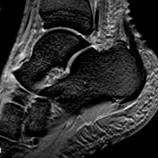

Наиболее информативными плоскостями сканирования для диагностики повреждения боковых связок являются аксиальная и коронарная; саггитальная - дает лишь возможность предположить повреждение.

| РИС 1. Саггитальная плоскость сканирования. Т1 и Т2 ВИ. Стрелками указаны повышенное скопление жидкости в переднем и заднем заворотах, в полости суставов – большеберцово-таранном и таранно-пяточном. |

При МР-томографии интенсивность сигнала задней малоберцово-таранной связки повышена на Т2 ВИ, контуры прерывисты.

| Рис 2. Аксиальная и коронарная плоскости сканирования. Т2 ВИ. Стрелкой показан полный разрыв задней малоберцово-таранной связки. В коронарной плоскости (б) можно лишь предположить наличие повреждения, а на аксиальной (а) это полностью подтверждено. | ||||

| Рис 3. Саггитальная плоскость сканирования. Т2 и Т1 ВИ. Стрелками указаны повышенное скопление жидкости в переднем и заднем заворотах, в полости суставов – большеберцово-таранном и таранно-пяточном. Повреждение каких-либо связок можно лишь предположить. |

Рис. 4. Левый – полный разрыв задней малоберцово-таранной связки (стрелкой показана часть связки в точке фиксации к малоберцовой кости). Правый – гематома в зоне повреждения (×). |